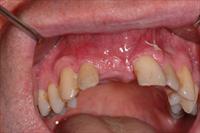

![]() 7. Four months post ridge split the site was uncovered in preparation for implant placement. |